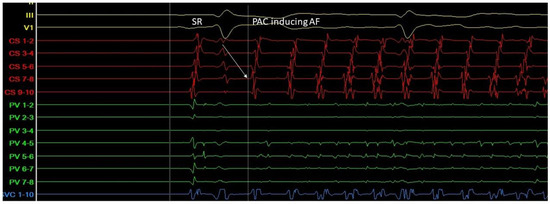

Triggers may originate from different regions (non-PV triggers), including the superior vena cava, crista terminalis, coronary sinus, left atrial appendage, left atrial posterior free wall, and ligament of Marshall [13]. Specific mapping protocols and isoprenaline have been used to address the significance of inducing, locating, and eliminating such non-PV triggers as a means to achieving better results in AF ablation in comparison to empirical PVI. However, this therapeutic strategy has not been established as a common practice [14] (Figure 10).

Figure 10. A. Atrial ectopic beat originates from the proximal aspect of the coronary sinus (arrow at the CS 7-8 electrogram)—a non PV trigger—and induces atrial fibrillation (G. Leventopoulos’ archive). PV: Pulmonary Vein. CS: Coronary Sinus.